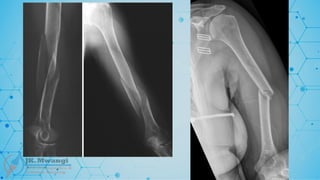

Galeazzi fracture

 A fracture of the radius with associated dislocation of the distal radioulnar joint

(DRUJ). Named after Ricardo Galeazzi, who described it in 1934